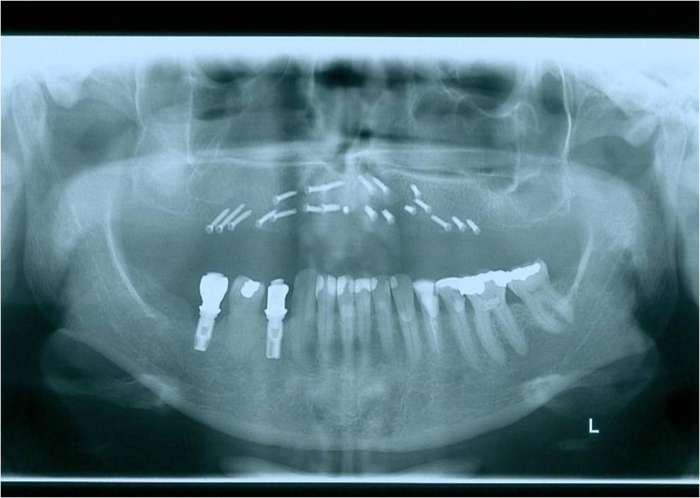

Raio x após prótese fixa provisória instalada